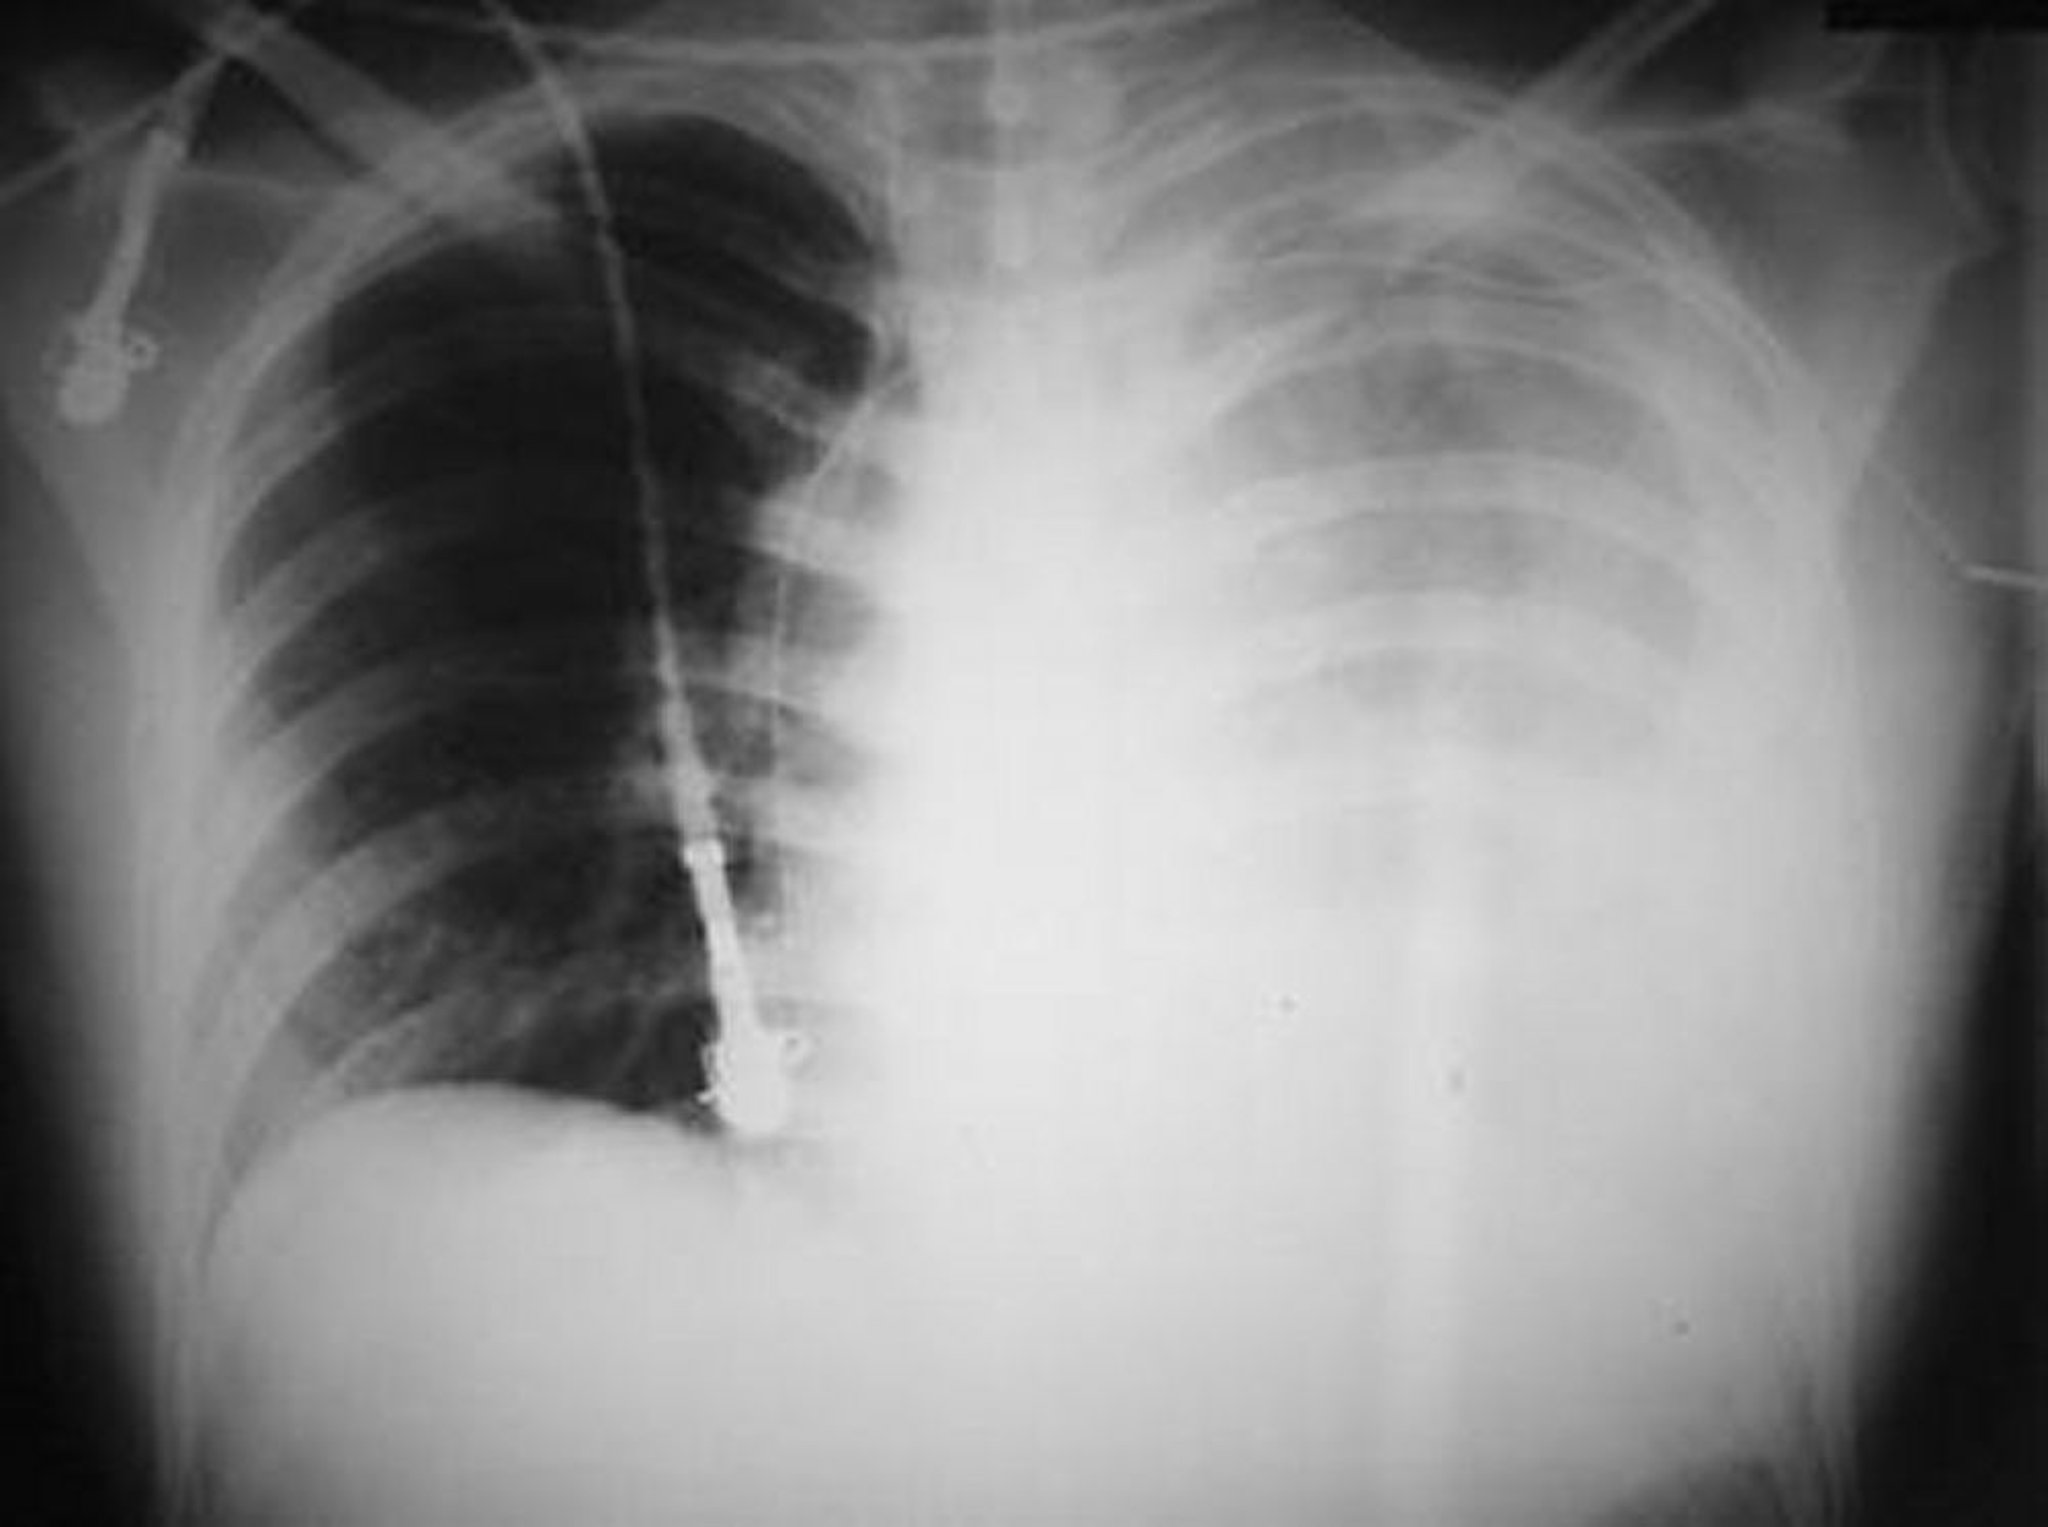

血胸

この写真には,左胸部に受けた銃創により生じた広範な血胸が写っている。